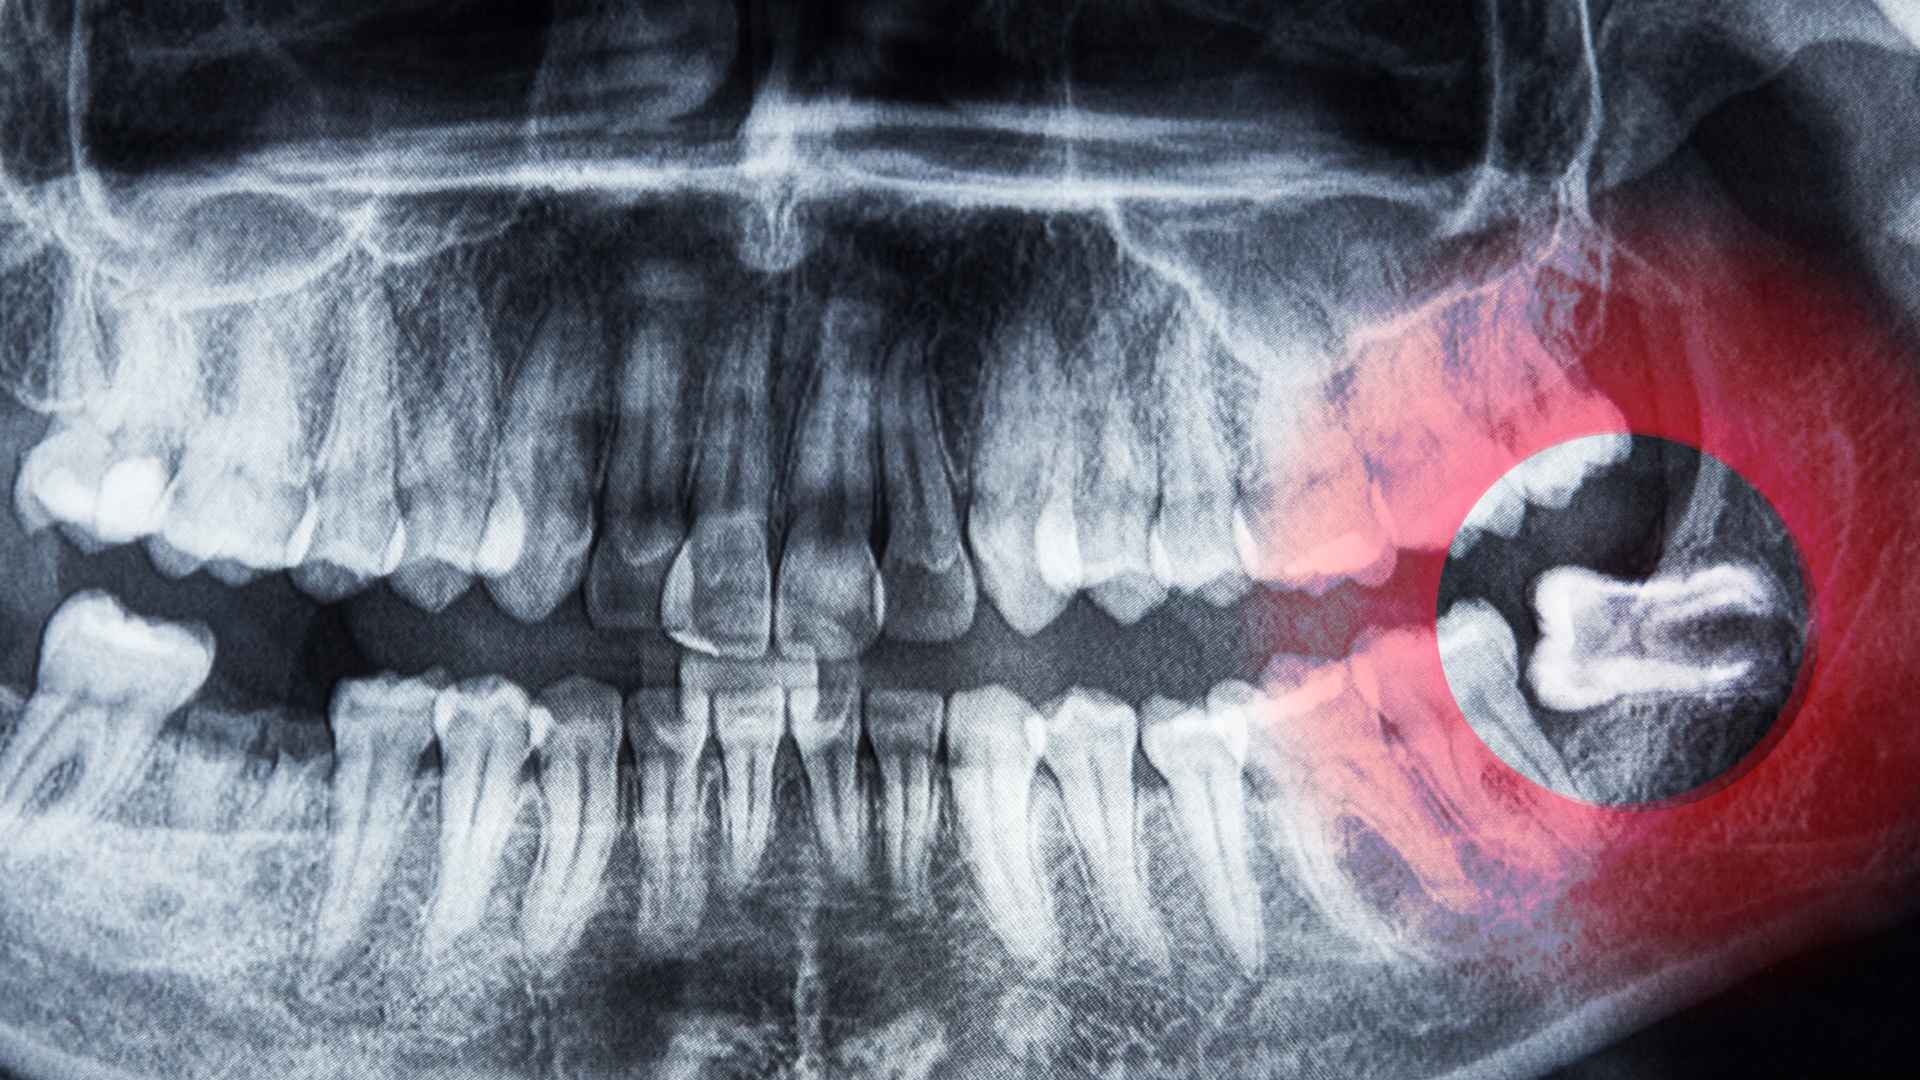

ที่ Time Dental Care เราเชี่ยวชาญด้านการผ่าตัดฟันคุดเพื่อช่วยจัดการความไม่สบายและป้องกันภาวะแทรกซ้อนที่เกี่ยวข้องกับฟันคุดที่มีปัญหา ฟันคุดเป็นฟันกรามซี่ที่สามที่มักขึ้นในวัยรุ่นปลายหรือผู้ใหญ่ตอนต้น หากฟันเหล่านี้ไม่มีพื้นที่เพียงพอในการขึ้น อาจทำให้เกิดความเจ็บปวด การติดเชื้อ และการเรียงตัวที่ผิดปกติของฟันอื่นๆ ทีมงานของเรามีทักษะและใช้เทคโนโลยีล่าสุดเพื่อให้การผ่าตัดเป็นไปอย่างปลอดภัยและมีประสิทธิภาพ ช่วยให้คุณฟื้นตัวได้อย่างรวดเร็วและสะดวกสบาย

เราจะเริ่มต้นด้วยการตรวจสอบอย่างละเอียดและเอ็กซเรย์เพื่อตรวจสอบตำแหน่งของฟันคุดและดูว่าจำเป็นต้องผ่าตัดหรือไม่